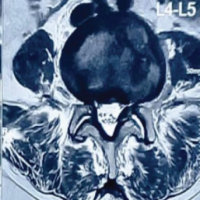

After taking due informed consent, the patient was taken to the operation theatre after 3 h of his arrival. He was placed in a supine position on the operating table. General anesthesia was administered and airway secured. A tourniquet was used at an appropriate pressure to aid in the procedure. The vascular surgery team was informed to be in standby mode. Removal of blade from the ankle was attempted first. Incisions were given at the entry and exit wounds, and a thorough wash was given. The metallic blade was removed with a single pull. Twists and turns were avoided to prevent any iatrogenic damage to the surrounding structures [4]. The area was thoroughly washed once more with normal saline and diluted betadine. Incisions were then carefully made without deep dissection at the entry and exit wounds in the knee. A light mallet was used to gently strike at the anterior aspect of the metallic blade in a controlled manner. The rod was then removed with a single pull. Along with the blade, the entire portion of the torn clothing was removed. Careful debridement was then done at both sites (knee and ankle) along with copious irrigation. Complete removal of the objects was confirmed clinically and through fluoroscopy. Gentle examination under anesthesia (Joint stability tests) was then performed, which suggested ligament injuries in both sites. The tourniquet was then deflated to check for any inadvertent arterial injury. SpO2 of the limb was >94%. Once the absence of arterial injury was confirmed, the wound was closed in layers. An above-knee anterior slab was put for adding stability of the joints and injured soft tissues. The post-operative radiograph documented the absence of any foreign bodies. Post-operatively an magnetic resonance imaging (MRI) was also done, which confirmed lateral meniscus and lateral collateral ligament injuries, anterior talofibular, calcaneofibular and tibiotalar ligaments in both the knee and the ankle, respectively. Absence of any retained clothing was also confirmed in the MRI. His post-operative hospital stay was mostly uneventful except for a superficial wound infection at the popliteal entry wound that eventually healed with IV antibiotics, single debridement, and regular dressings. The sutures were removed at the end of the 2nd week. The patient was then discharged in satisfactory clinical condition with the explanation that he may eventually require knee and ankle arthroscopy and reconstruction of some of the critically torn ligaments of the knee and ankle joint if these fail to heal satisfactorily (Fig. 6, 7, 8, 9, 10).